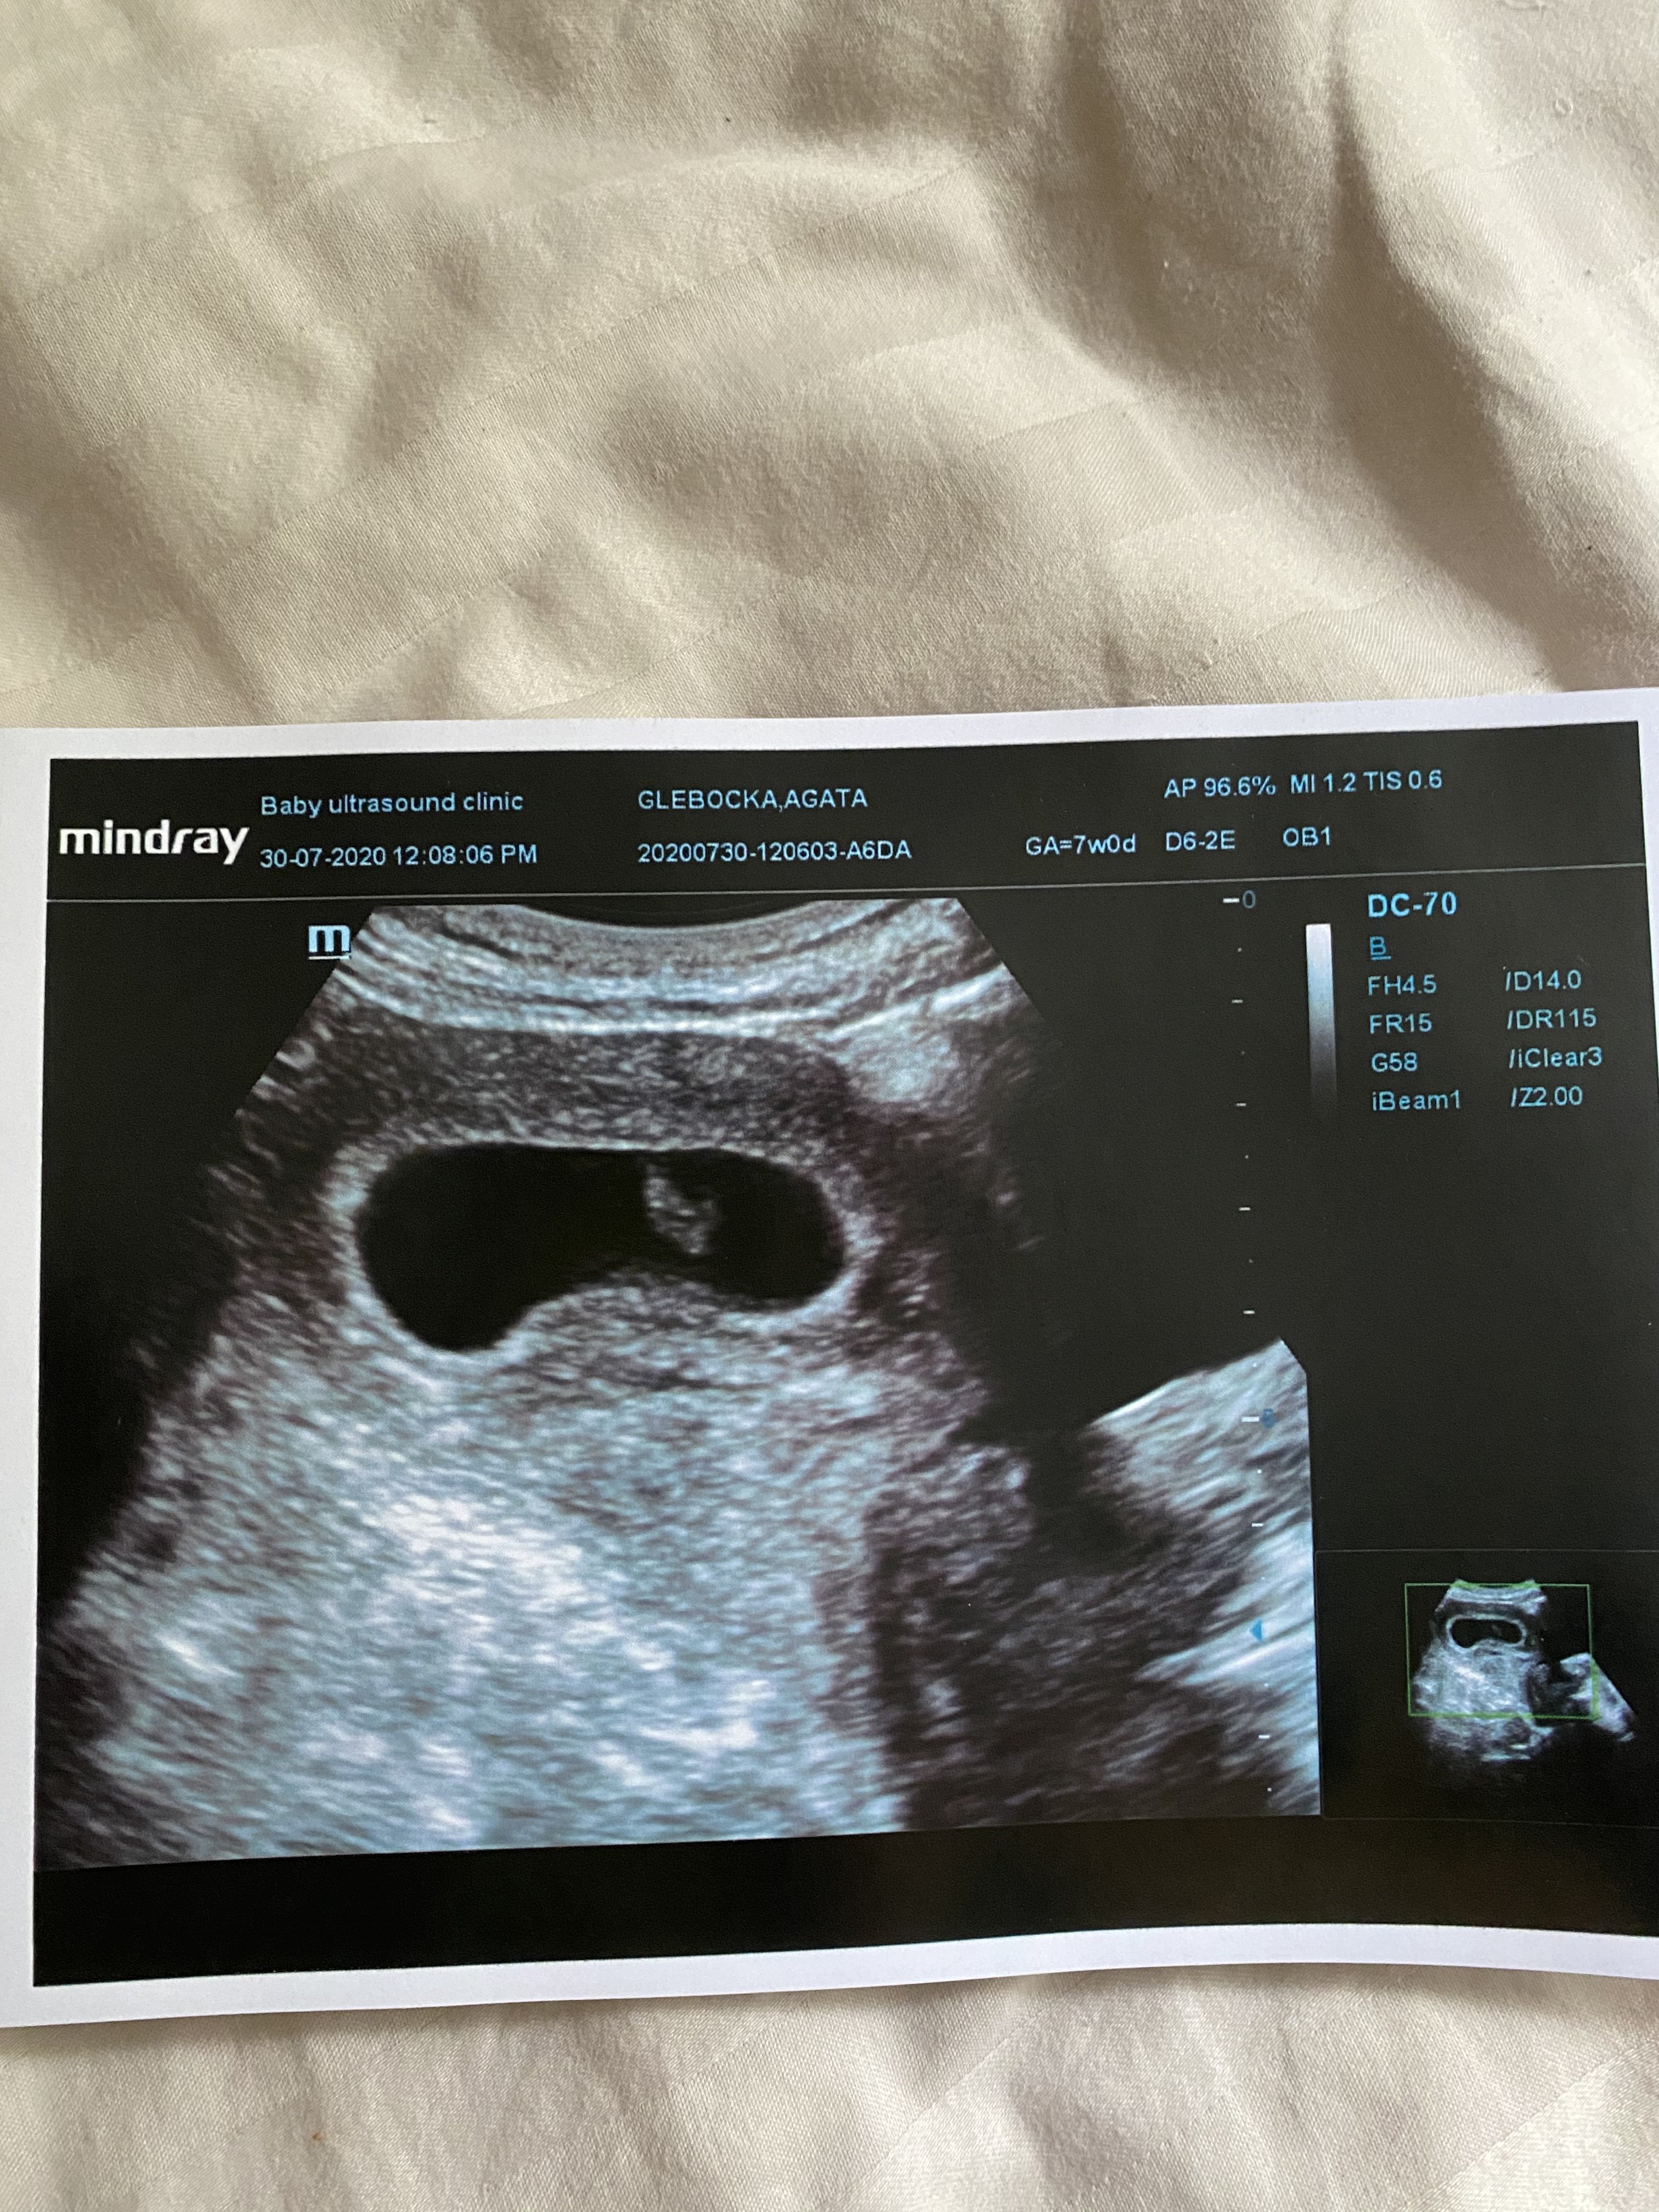

Hej dziewczyny Ja wrocilam wlasnie z usg, nie daje rady nadrabiac bo ciagle w robocie. Data z usg i z ostatniej miesiaczki dokladnie taka sama 7 tyg dzis data porodu na 18.03

Załączniki